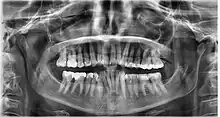

Dental

Dental examination is a method of body identification that involves the comparison of antemortem and postmortem dental records, such as radiographs and photographs.[18] The jaw is analysed to detect any peculiarities in the teeth or any diseases.[18] In the scenario where skin prints are unable to assist in the process of identification, dental examination can be used.[19] The Forensic Dentistry and Anthropology Center of the Dental Faculty of Piracicaba analysed radiographs and dental records of a "surgically implanted orthopedic plate"[19] to successfully identify a burned body. The success of dental identification can be tainted if the individual has endured a physically traumatic experience that has caused damage to their teeth and jaw.[20] In this scenario, DNA identification is used in the process of body identification.